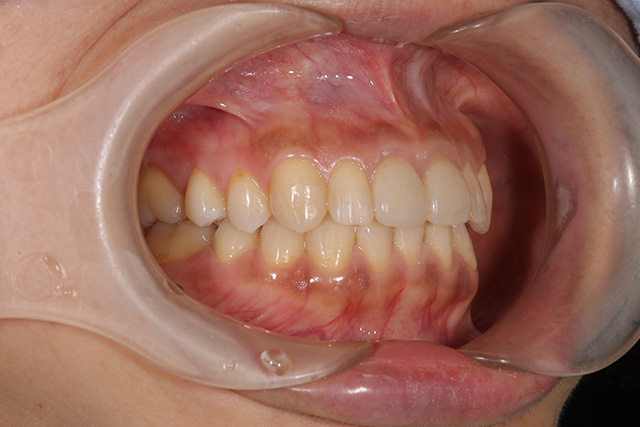

審美症例